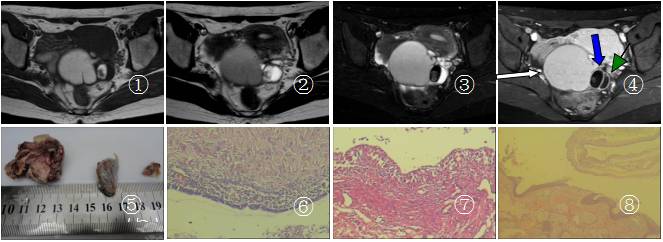

图1 为T1WI序列示盆腔内肿块信号不一,右份较大,呈高信号,中份呈高低混杂信号,左份低信号 图2 T2WI序列示病灶右份呈稍低信号,中份呈高信号信号,左份呈高信号 图3 脂肪抑制T2WI右份呈中份信号减低 图4增强病灶未见强化,病灶右份为白箭所指,中份为蓝箭所指,左份为绿三角形尖所指 图5为手术切除肿物 图6、7、8 三个肿物的病理图片。

B超:左附件区囊、实性混合团块,考虑左侧畸胎瘤。彩色多普勒显像(CDFI):未见明显血液信号。MR表现:盆腔内子宫后偏上方见大小约78mm×55mm肿块影。肿块分隔成右侧、中部、左侧份不同信号区。右份、中份、左份病灶T1WI、T2WI信号不同;T2WI脂肪抑制中份区域高信号减低。DWI肿块的信号未见增高;增强后病灶未见强化。

术中所见:左卵巢囊性病变约80mm×70mm×6mm,与盆后壁及子宫侧壁粘连,右侧份为咖啡色囊液;中份病灶有毛发及少量实性组织,左份病灶为淡黄色液体。术后诊断:(1)左卵巢畸胎瘤;(2)左卵巢巧克力囊肿;(3)左卵巢单纯性囊肿。

病理所见:送检灰白色囊性肿物三个,/镜检肿物最大者见大量异位的子宫内膜组织,大量纤维组织增生伴多量的含铁血黄素沉积。中份肿物呈囊性结构,囊壁被覆假复层柱状上皮、鳞状上皮,其下可见皮肤附属器组织及淋巴等组织,各种组织成分分化成熟。另检囊肿以纤维组织为囊壁,未见衬覆上皮。病理诊断:(1)左卵巢子宫内膜异位囊肿;(2)左卵巢成熟性囊性畸胎瘤;(3)左卵巢符合单纯性囊肿。